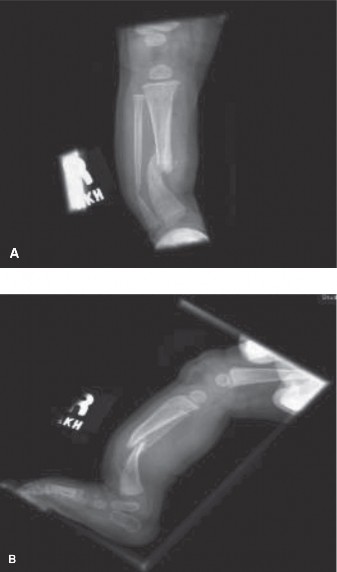

CASE 33 A 3-year-old girl presents to your clinic with her mother. The patient’…

CASE 30 A 1-year-old male is brought to your clinic by his parents for evaluati…